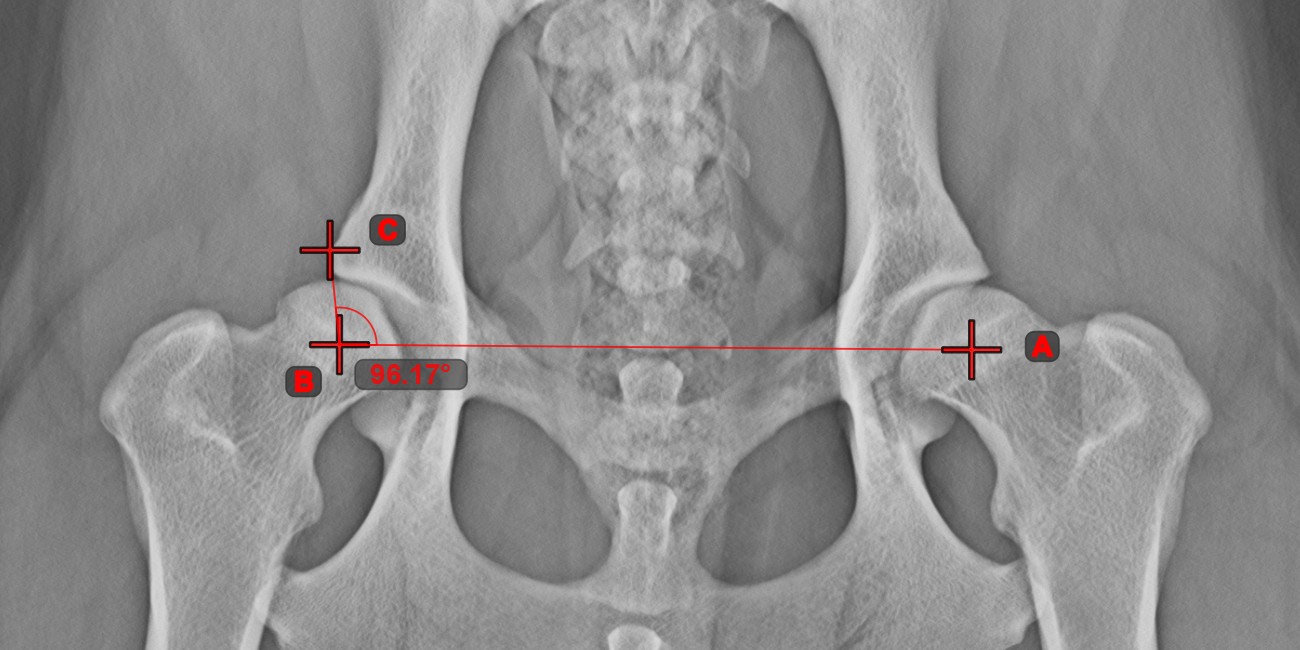

Angle of Lines¶

Select the tool from the left toolbar and assign it to one of the available mouse buttons. Start by selecting the first line from the ones already drawn on the scene, or place the start and end points to create the line. Follow the same steps for the second line of the measurement. The angle between the two lines will be automatically calculated.

Modify the start and end points of both lines by using the Select/Move Item tool. The angle between the two lines will be automatically recalculated.

Information

If two lines do not intersect directly, the angle of their extended projections on the scene will be calculated.